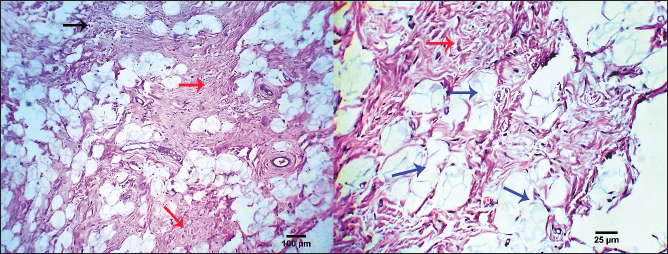

The clinical history and gross pathology of the current case revealed a necrotizing dermatological condition that was characterized by the presence of numerous sizable, red–purple, nonpruritic skin lesions. The necropsy findings revealed the presence of diffuse fat necrosis and pancreatic nodular hyperplasia. The larger lesions had substantial dimensions and featured soft, highly pigmented cores that harbored an aseptic, thick, hemoglobin-infused substance. The histopathological analysis unveiled the presence of necrotizing panniculitis, characterized by the necrosis of subcutaneous fat tissue. In addition, there was observed capillary dilation, marked infiltration of leukocytes, and localized proliferation of mesenchymal cells (Fig. 13).

Fig. 13. Photomicrograph showing necrotizing panniculitis (subcutaneous fat necrosis), capillary dilation (dark blue arrows), intense leucocytic infiltration (black arrow), and focal mesenchymal proliferation (red arrows). Scale bars 25, 100 µm.

Ultimately, the clinical history and macroscopical pathology of the present individuals pointed to a necrotizing dermatological illness characterized by several large, reddish–purple, nonpruritic lesions. A necropsy revealed diffuse fat necrosis and pancreatic nodular hyperplasia. The larger lesions had mushy, highly discolored centers that were filled with a blood-tinged, viscous, sterile fluid. Necrotizing panniculitis (subcutaneous fat necrosis), capillary dilatation, strong leucocytic infiltration, and localized mesenchymal growth were all found during the histopathological examination. The results of this investigation were consistent with the results of the research that were previously cited (DeManuelle and Stannard, 1998; Contreary et al., 2015).